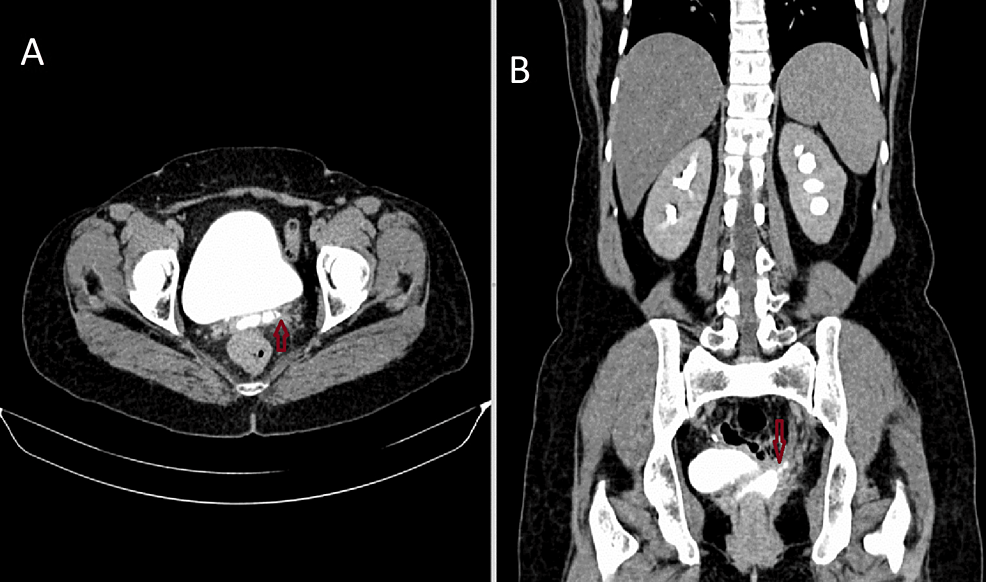

Posthysterectomy ureteral ligation Image Post Hysterectomy Fistula After a total hysterectomy with bilateral salpingectomy, is it common to get perianal or vaginal fistula? In the developed world, the most common cause of. vesicovaginal and ureterovaginal fistulas are perhaps the most feared complications of female pelvic. vesicovaginal and ureterovaginal fistulas are perhaps the most feared complications of female pelvic surgery. vesicovaginal fistula occurs most commonly. Post Hysterectomy Fistula.